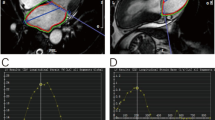

Table 1 summarises the clinical characteristics of the STEMI patients and LV function and volumes as determined by cine CMR. The images obtained from a 70 year-old male with an acute sub-endocardial scar in the lateral left ventricular wall are shown in Fig. 1.

Cine images at a end diastole and b end systole showing a wall motion defect in the anterolateral and inferolateral segments, and c the corresponding LGE image. d Graphical representations of circumferential strain throughout the cardiac cycle, as determined by DENSE. AS antero-septal, A anterior, AL antero-lateral, IL inferolateral, I inferior, IS inferoseptal